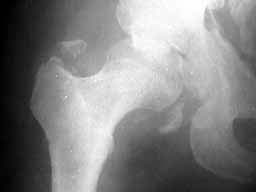

Seeking advice on management of 50 years old male who presented with infected fracture dislocation right hip with complete sciatic nerve palsy three months after injury. Xrays initial and current and CT scan Current images attached.

AP now